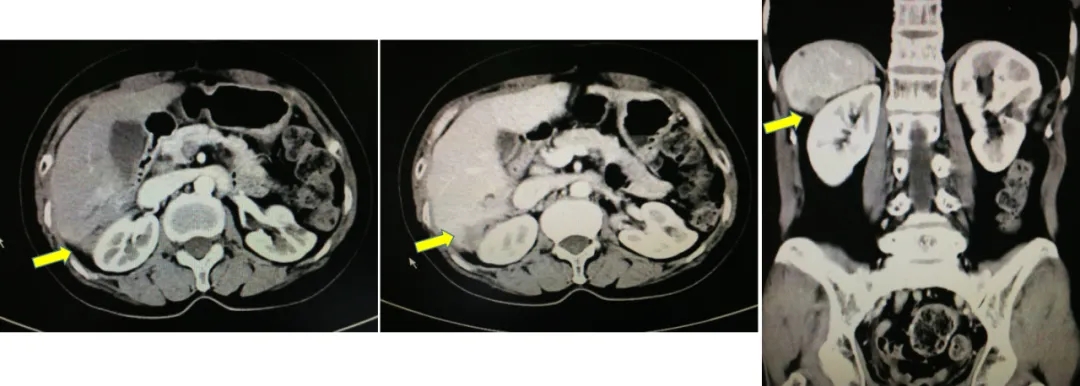

2017-10-26当地查CA125水平为46.3U/ml,2017-12-4我院查CA12水平为110.9U/ml,CT显示肝肾间隙及右肝包膜下片状影较前增大,考虑疾病复发。

CT检查结果

2019.5.8查CA125为78.3U/ml,CT显示右肝后缘欠光整伴片状低密度影。基因检测BRCA1致病性突变,诊断为铂敏感复发卵巢癌。2019.5-2021.4入组BGB-290-102单臂临床研究,口服PARP抑制剂治疗。

2021.4.23复查CA125上升至70.2U/ml。2021.4.24 CT:肝肾隐窝病灶增大,考虑复发。患者退出BGB-290临床试验。